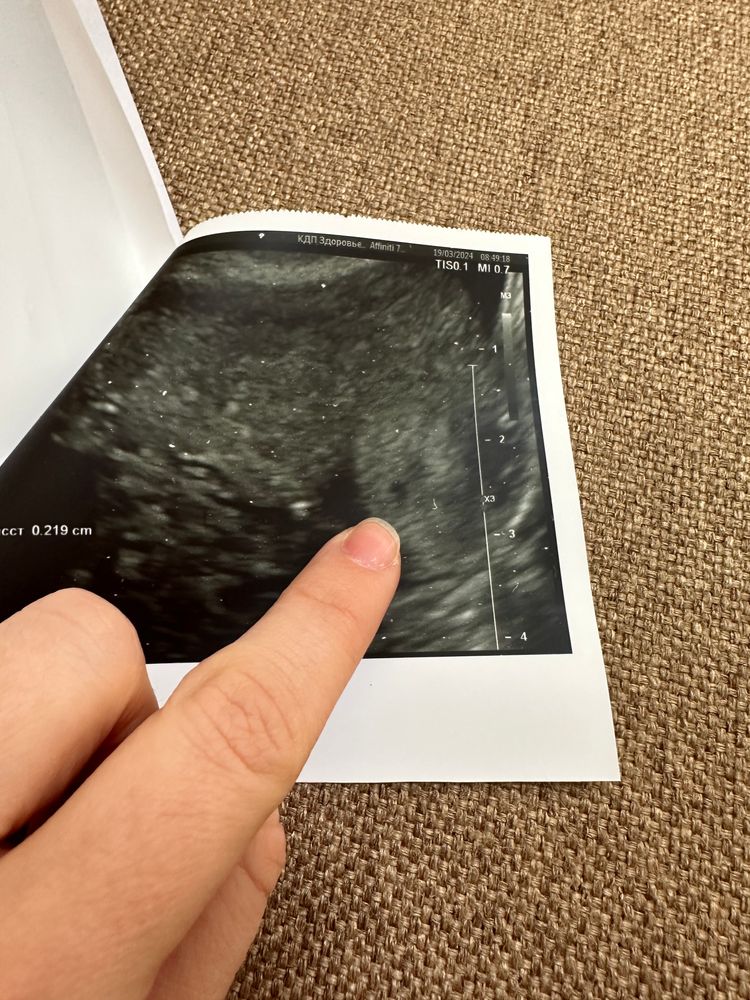

Поодное яйцо в углу матки

Посмотрите снимок узи, у кого так было, чем закончилось? Раньше писали матка седловидная, сейчас пишут нормальная

срок 4 недели , пя в левом углу матки, рядом еще одно под вопросом

я так понимаю пятно черное справа это труба?